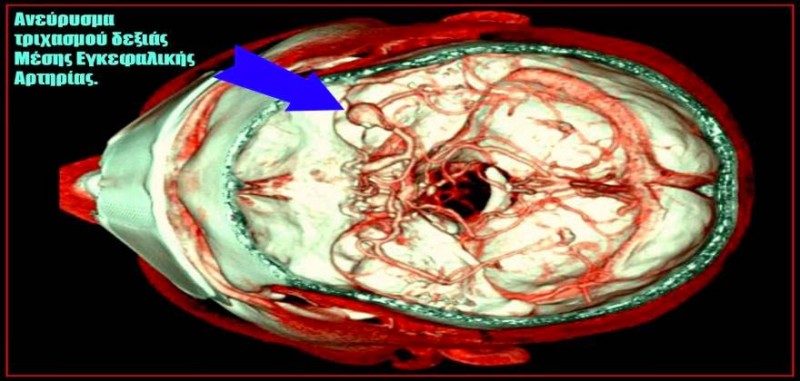

Ένας θρόμβος αίματος μέσα στο σώμα μας μπορεί να είναι πολύ επικίνδυνος και δυνητικά απειλητικός για τη ζωή. Ο Aaron W. Aday, MD λέει, «Οι θρόμβοι παίζουν επίσης σημαντικό ρόλο στο εγκεφαλικό επεισόδιο. Κάποιες από τις πρώτες αρτηρίες στις οποίες φτάνει το αίμα αφού φύγει από την καρδιά, είναι οι αρτηρίες στον εγκέφαλο και ένας θρόμβος που διέρχεται από την καρδιά προς τις αρτηρίες αυτές, μπορεί να προκαλέσει εγκεφαλικό επεισόδιο».

Πολλοί άνθρωποι υποφέρουν από χρόνιους πονοκεφάλους, αλλά αυτοί που σχετίζονται με τη θρόμβωση είναι πολύ σοβαροί. Στην πραγματικότητα, μπορεί να είναι αρκετά ισχυροί για να σας καταστήσουν ανίκανους για εργασία και να δυσκολεύεστε να εστιάσετε. Μπορεί επίσης να διαπιστώσετε ότι η λήψη φαρμάκων δεν σας κάνει να αισθανθείτε καλύτερα. Εάν συμβαίνει αυτό, αναζητήστε ιατρική βοήθεια, καθώς αυτό θα μπορούσε να υποδηλώνει θρόμβωση στον εγκέφαλο.